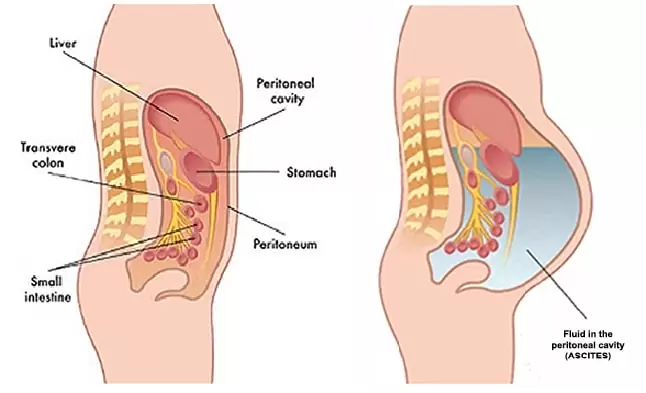

Peritoneal Cancers

Cancer that has spread to the lining surfaces of the peritoneal (abdominal) cavity from ovarian cancer, primary colorectal cancer, appe...